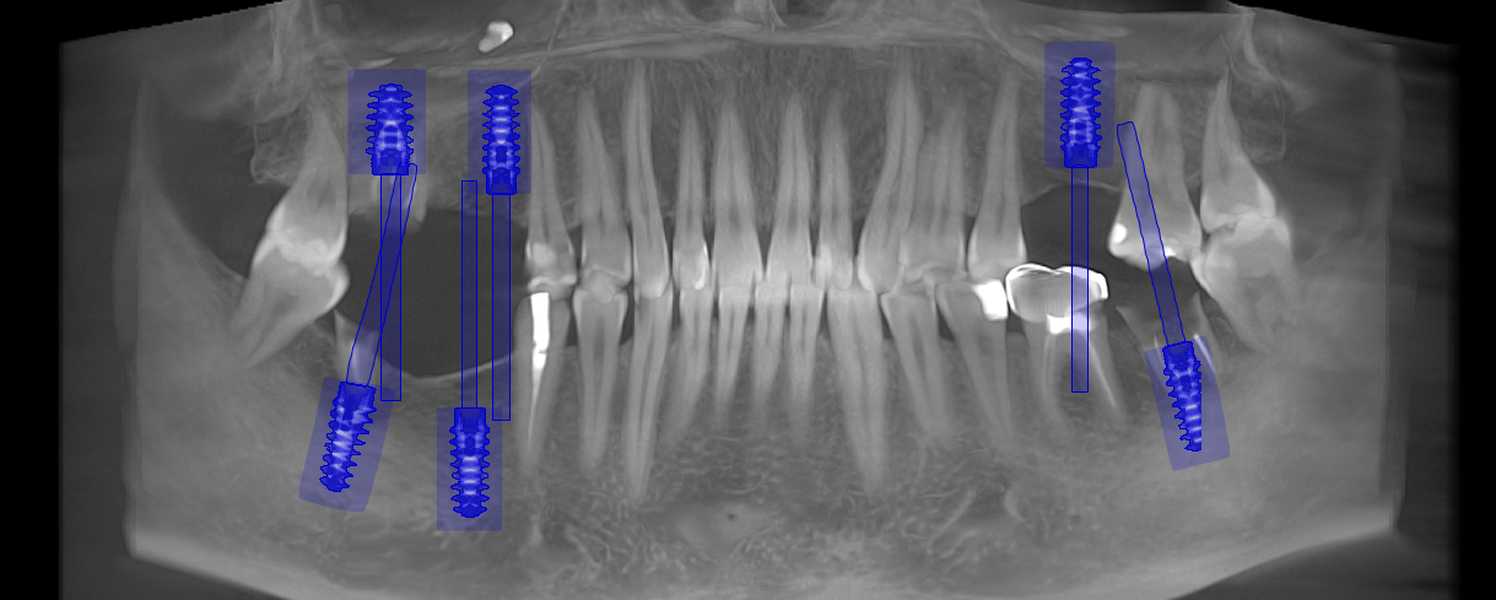

- Consultația inițială și planificarea tratamentului (inclusiv tomografie CBCT)

- Inserarea implanturilor dentare (chirurgie ghidată digital)

- Proteze pe sistem de bare sau capse (All-on-4, All-on-6)

- Tehnologie digitală de ultimă generație – scanare 3D, design asistat digital

- Chirurgie implantologică ghidată, minim invazivă